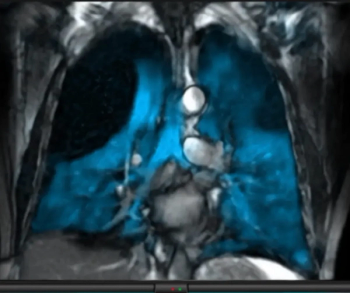

Previously approved for MRI lung ventilation evaluation in adults and children 12 and older, the hyperpolarized contrast agent Xenoview can now be utilized for pediatric patients six years and older.